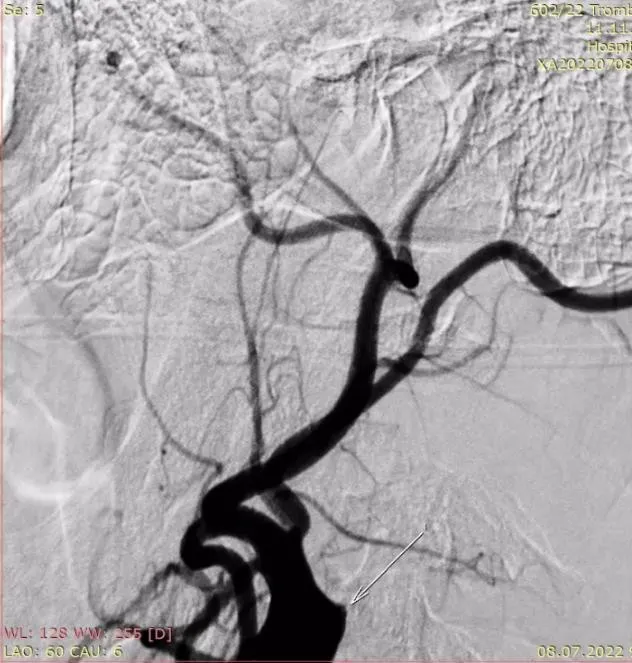

Для анестезіологічного забезпечення механічної тромбектомії застосовували седацію зі збереженням свідомості із забезпеченням кисневої підтримки через маску – 4 л/хв. АТ при ініціальному вимірюванні дорівнював 183/95 мм рт.ст. та не знижувався до моменту реперфузії басейну СМА. Час від початку захворювання до пункції стегнової артерії в ендоваскулярній операційній – 1255 хвилин. Оскільки дані МСКТ – ангіографії вказували на тандемну оклюзію (устя лівої ВСА та сегменту М1 лівої СМА) та демонстрували хорошу колатеральну компенсацію басейну лівої СМА, трансфеморальним доступом операційним провідниковим катетером відразу була проведена катетеризація лівої загальної сонної артерії без етапу діагностичної ангіографії. Цифрова субтракційна ангіографія дозволила з’ясувати місце відходження лівої ВСА від загальної сонної артерії та за допомогою балонного катетера для черезшкірної ангіопластики (percutaneous transluminal angioplasty balloon catheter) сформувати канал на рівні тромбованої атеросклеротичної бляшки ВСА (рис. 4) з метою проведення за межі оклюзії у дистальному напрямку операційного провідникового катетера.

Рисунок 4. Цифрова субтракційна ангіографія, лівий каротидний басейн, ліва косо- фронтальна проекція. Місце відходження лівої ВСА від загальної сонної артерії (червона стрілка). Наповнення балонного катетера на рівні тромбованої атеросклеротичної бляшки (балон позначено жовтою стрілкою).